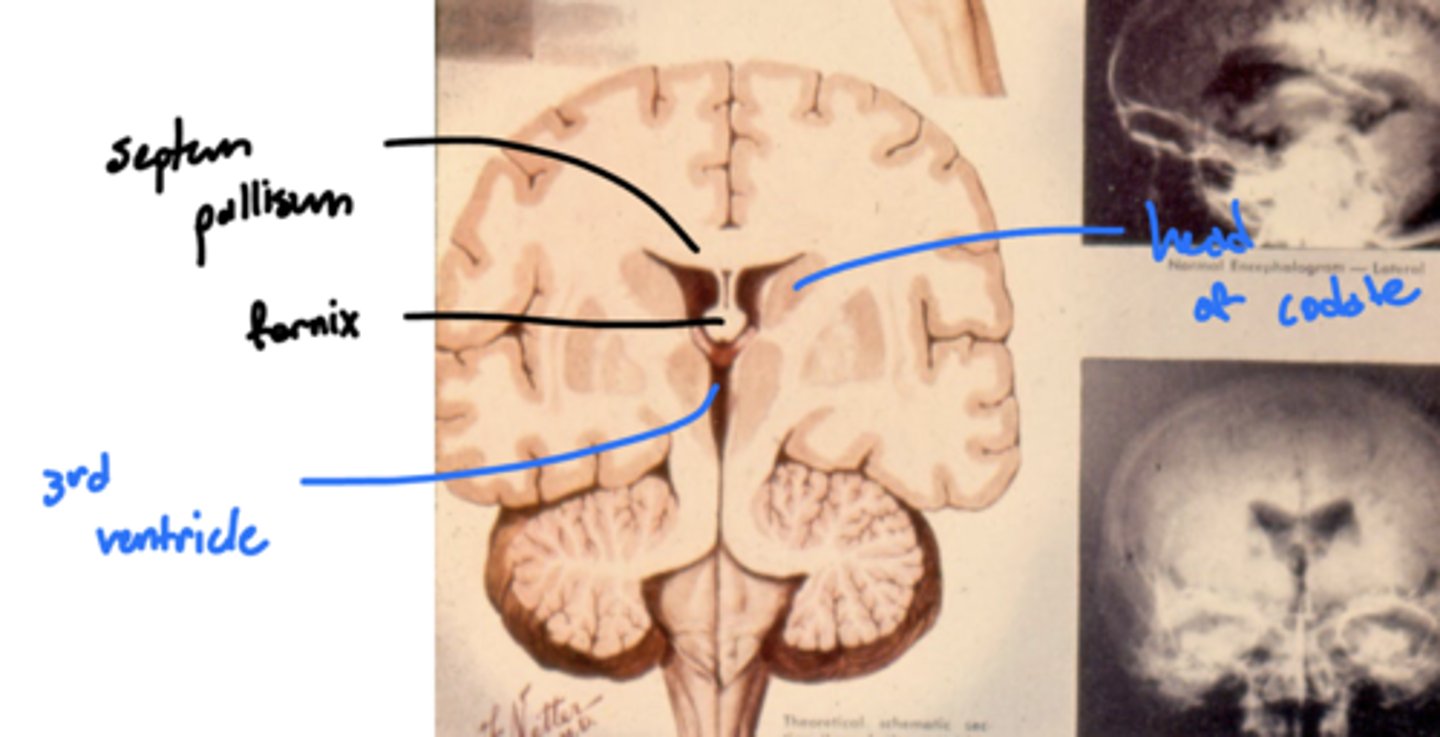

What are the lateral walls of the third ventricle?

thalamus and hypothalamus

the neuronal connection between the two thalami

What does the massa intermedia pass through?

3rd ventricle

What is the pathway from the hippocampus to the anterior nuclei of the thalamus?

1. hippocampus

2. fornix

3. mammillary nuclei

4. mammillothalamic tract

5. anterior nuclei (thalamus)